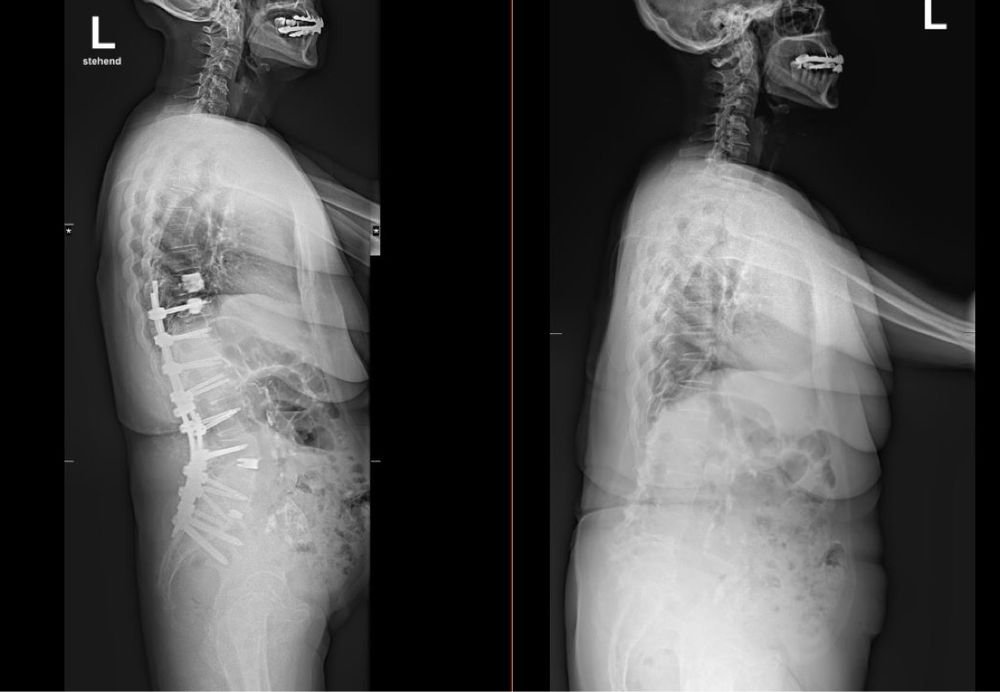

Post image

Mastering the realignment of a kyphotic spine demands years of dedicated practice. Do not assume that a residency and a single year in fellowship alone will equip you with such expertise to manage without helping assistance.